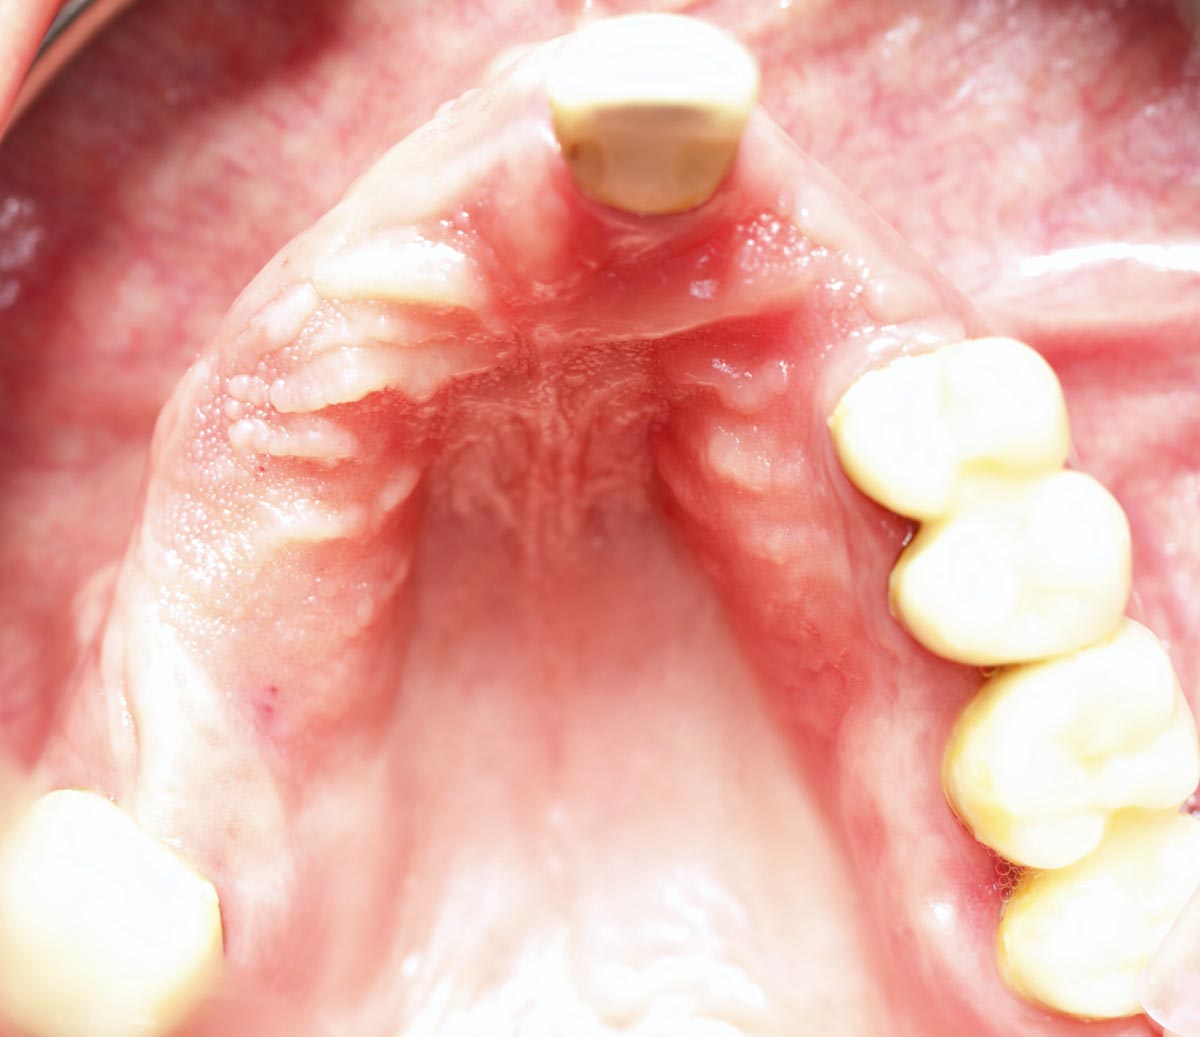

Pre-operative clinical situation: severe atrophy of the maxillary bone